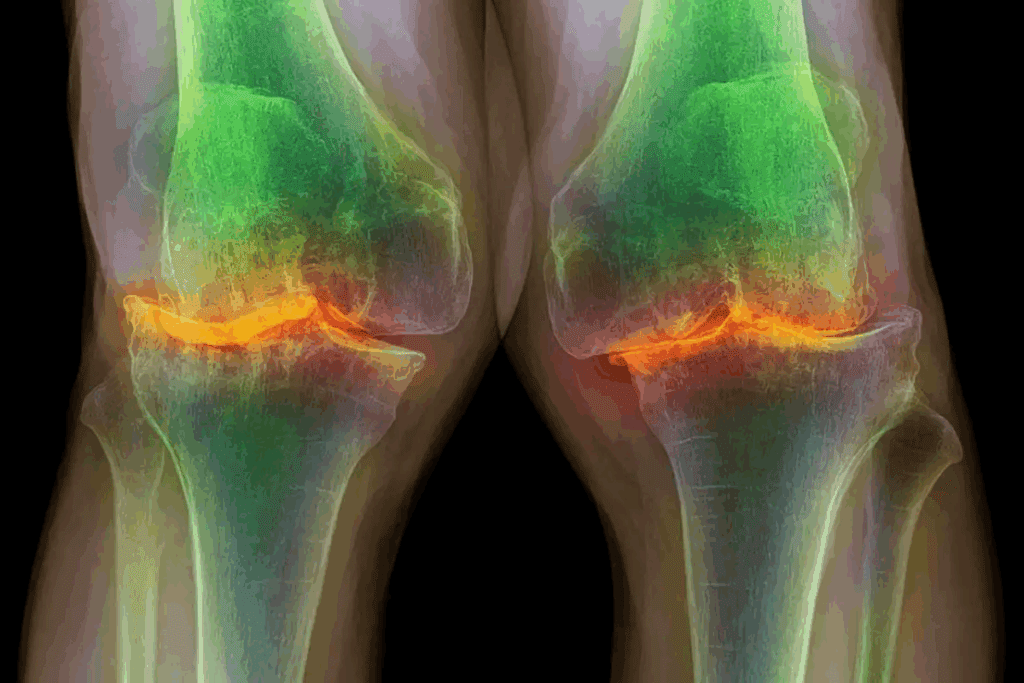

X-Ray Findings in Osteoarthritis

X-rays help see joint damage in osteoarthritis. They show joint space narrowing, bone spurs, and other signs. X-rays are great for checking how bad osteoarthritis is and if it’s getting worse.

Knee Osteoarthritis Diagnosis

To diagnose knee osteoarthritis, doctors use both clinical checks and imaging. They look at symptoms like pain and stiffness. They also check joint mobility and stability.

X-rays help see joint space narrowing and bone spurs. These signs are common in osteoarthritis.